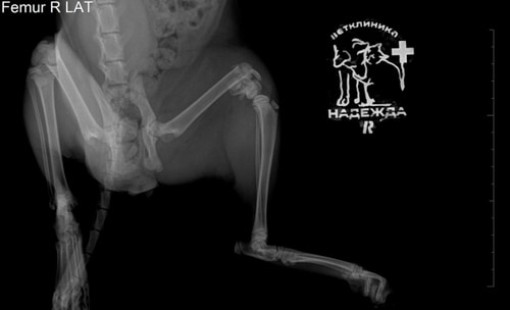

Случаи из практики

Ветеринарная клиника Надежда

За более чем 30-ти летнюю практику наши ветеринары сталкивались в различными случаями болезней и травм животных. Это дало нам огромный опыт в лечении и реабилитации. Мы беремся даже за самые сложные случаи! С любовью и заботой относимся к животным, стараемся сделать так, чтобы они испытывали минимум дискомфорта во время лечения и реабилитации.